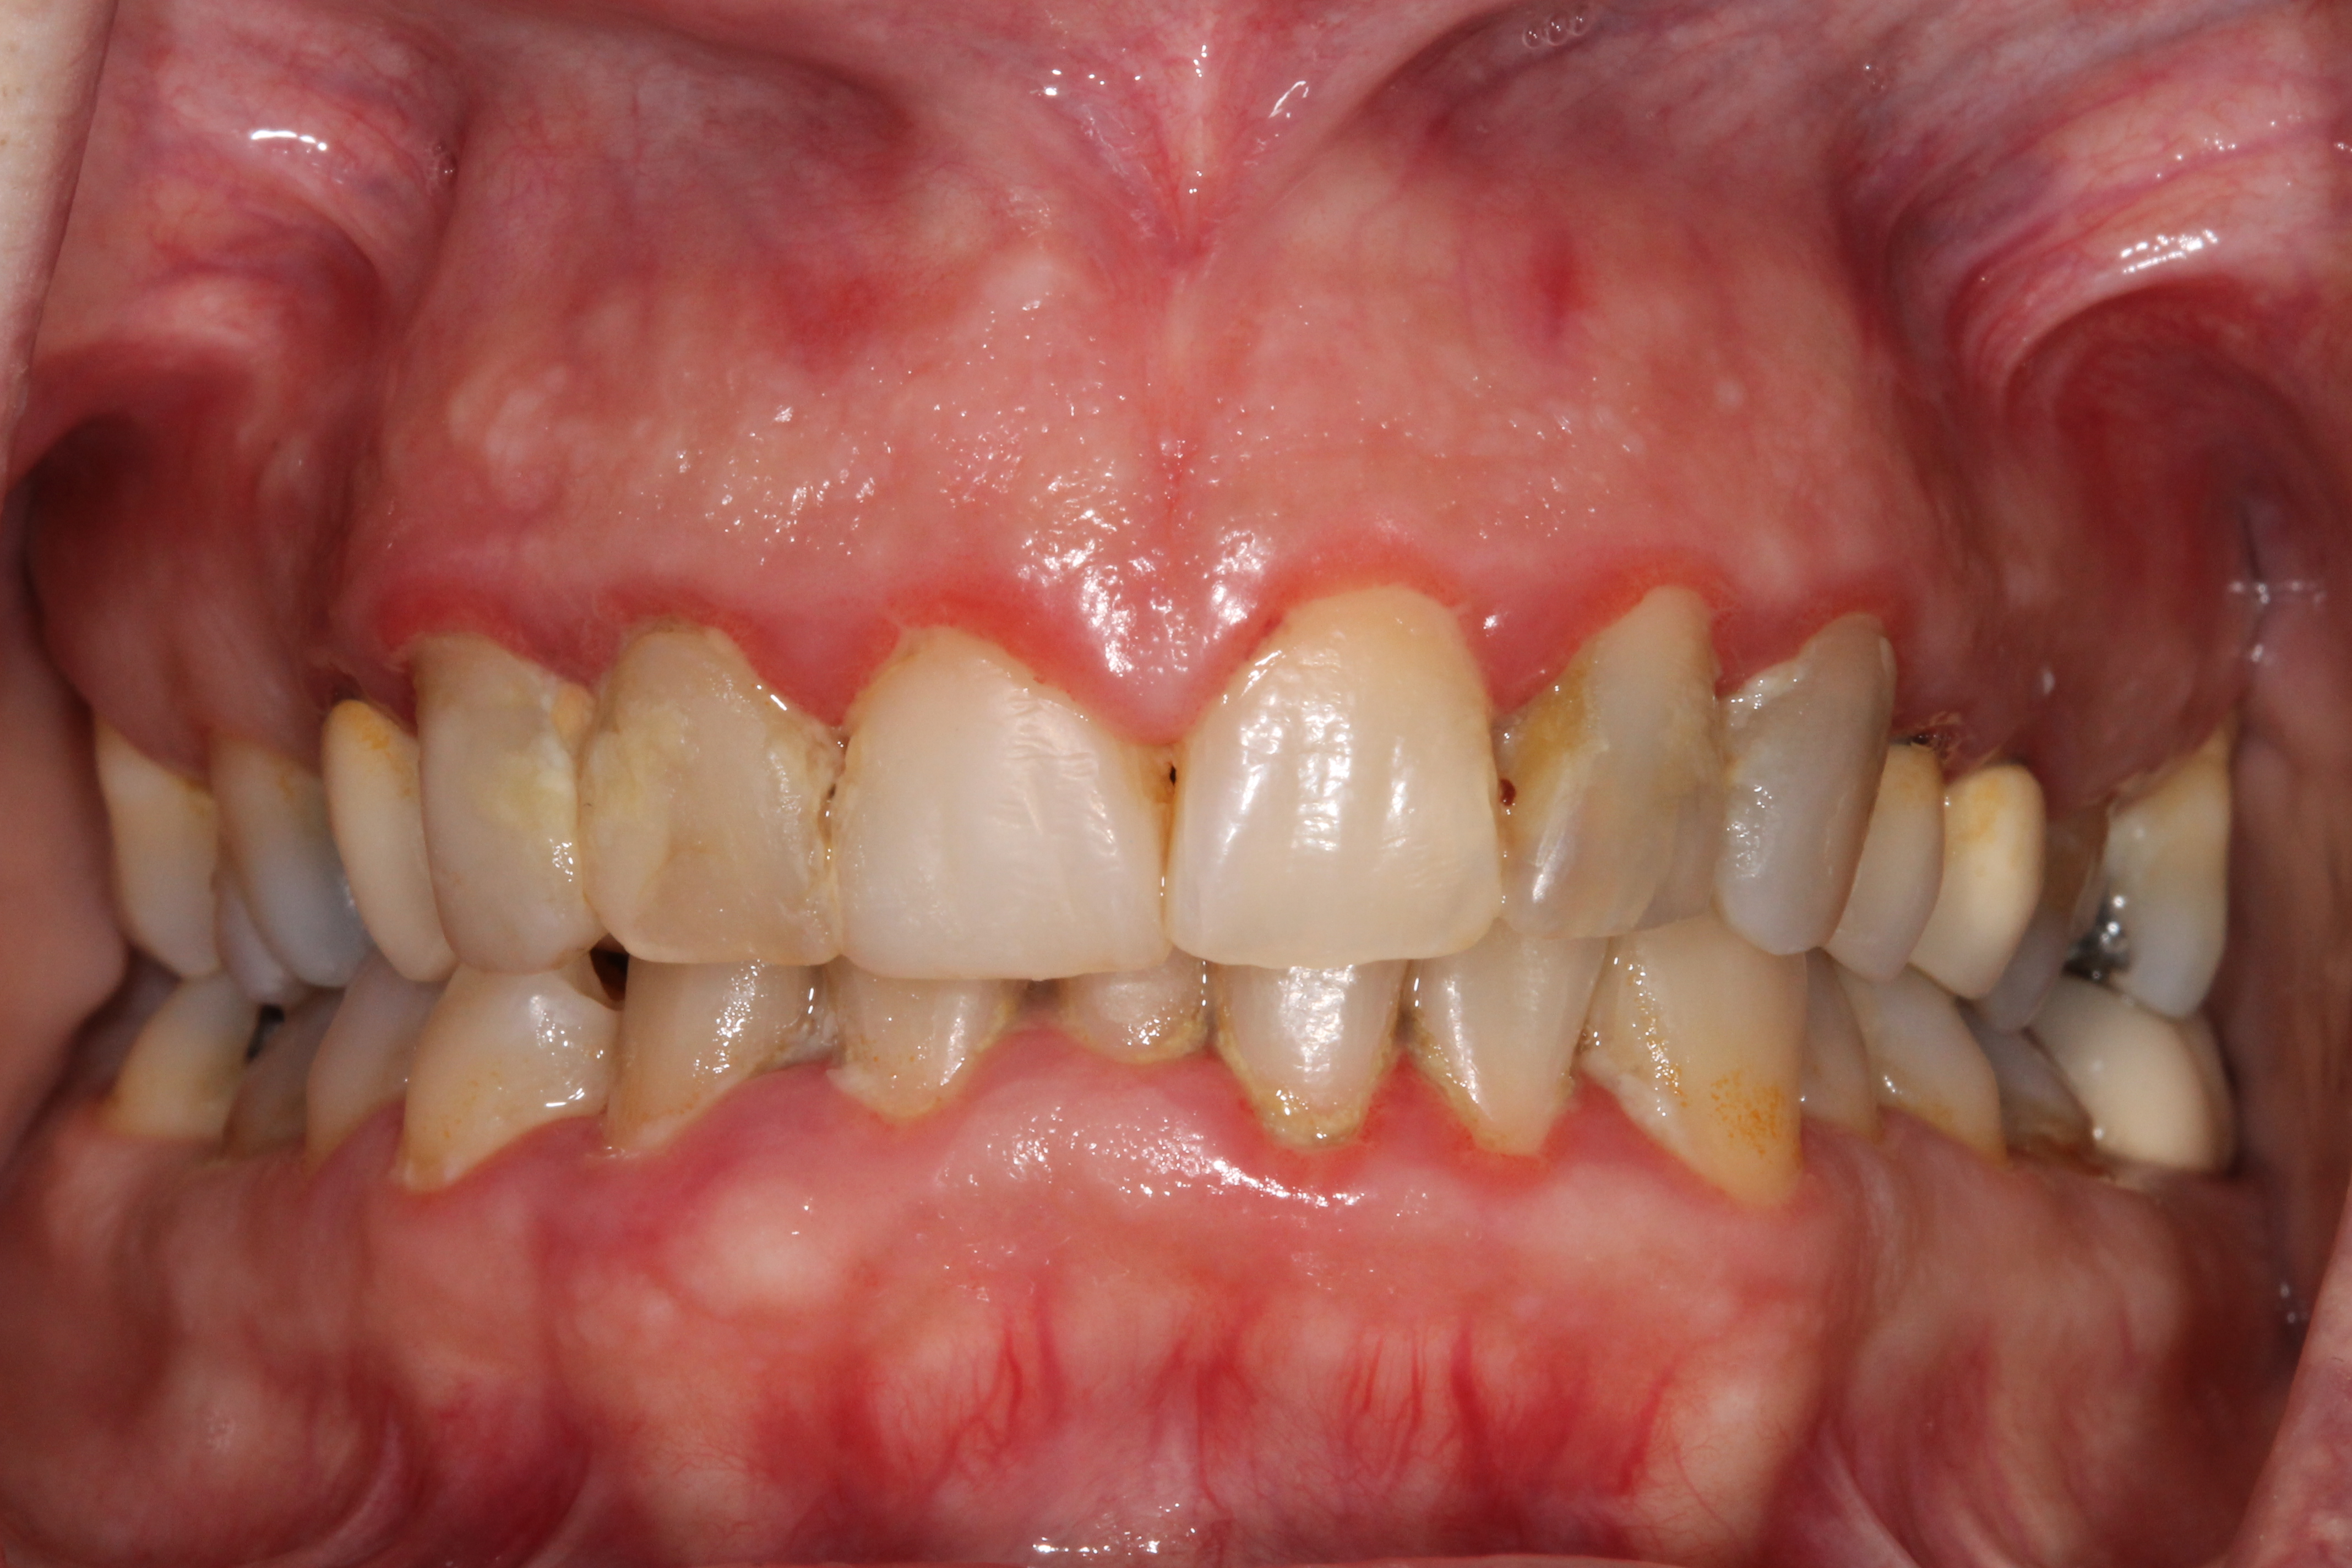

ΕΝΔΕΙΚΤΙΚΑ ΠΕΡΙΣΤΑΤΙΚΑ ΤΗΣ ΝΟΣΟΥ

αρχικό στάδιο

Ουλίτιδα

Η ουλίτιδα είναι η φλεγμονή μόνο των ούλων και αποτελεί την αρχική μορφή της περιοδοντικής νόσου.

Στην ουλίτιδα, μετά τη θεραπεία, οι περιοδοντικοί ιστοί επανέρχονται στην αρχική φυσιολογική τους μορφή (αντιστρεπτή βλάβη). Εάν όμως δεν θεραπευτεί, στις περισσότερες περιπτώσεις η ουλίτιδα, και σε χρόνο που δεν γνωρίζουμε και δεν μπορούμε να προβλέψουμε, εξελίσσεται σε περιοδοντίτιδα.